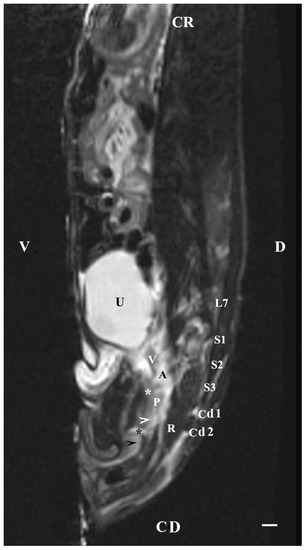

On the sagittal imaging of bulbourethral glands on T2-weighted sequences, the glandular findings could be visualized as soft-tissue, hyper-intense (compared to the rectum) and homogeneous structures. The studied glands showed a low intensity compared to the hyper-intense findings of the prostate complex, pelvic diaphragm and penile root. They had a higher intensity compared to the hypo-intense vesicular glands. The perineal location of the bulbourethral glands close to the pelvic diaphragm, penile root and rectum was determined. Topographically, the studied glandular findings were observed in the area of the pelvic outlet, at the caudal end of the pelvic urethra and ventrally to the bodies of the first and second caudal vertebrae. The image of the glands was oval and had a lack of differentiation between the stroma and parenchyma (Figure 8).

Figure 8. T2-weighted sagittal image of rabbit pelvis: V—ventral; D—dorsal; CR—cranial; CD—caudal. Bulbourethral glands (horizontal white arrow), vesicular glands (V), prostate gland complex (P), the pelvic part of the urethra (white star), the caudal part of the urinary bladder (U), adipose tissue (A), rectum (R), pelvic diaphragm (black star), root of the penis (white cross), L7—seventh lumbar vertebra, S1—first sacral vertebra, S2—second sacral vertebra, S3—third sacral vertebra, Cd1—first caudal vertebra, and Cd2 second caudal vertebra. Line—10 mm.

The sagittal imaging of the bulbourethral glands in T1-weighted sequences presented the glandular findings as soft-tissue, irregularly oval, with unclearly defined borders (capsule) and parts (stroma and parenchyma). The glands presented increased intensity compared to that of the rectum and decreased intensity compared to that of the pelvic diaphragm. The bulbourethral glands had a higher intensity than the vesicular glands and the prostate complex. The glandular image was found in the perineal region, cranial to the root of the penis, and at a close distance to the pelvic diaphragm. Topographically, the localization of the glandular findings was visualized at the outlet of the pelvic cavity, ventral to the first two caudal vertebrae and the rectum (Figure 9).

Figure 9. T1-weighted sagittal image of rabbit pelvis: V—ventral; D—dorsal; CR—cranial; CD—caudal. Bulbourethral glands (horizontal white arrow), the pelvic part of the urethra (white star), vesicular glands (V), prostate complex (P), pelvic diaphragm (black star), root of the penis (black horizontal arrow), urinary bladder (U), adipose tissue (A), rectum (R), L7—seventh lumbar vertebra, S1—first sacral vertebra, S2—second sacral vertebra, S3—third sacral vertebra, Cd1—first caudal vertebra, and Cd2 second caudal vertebra. Line—10 mm.